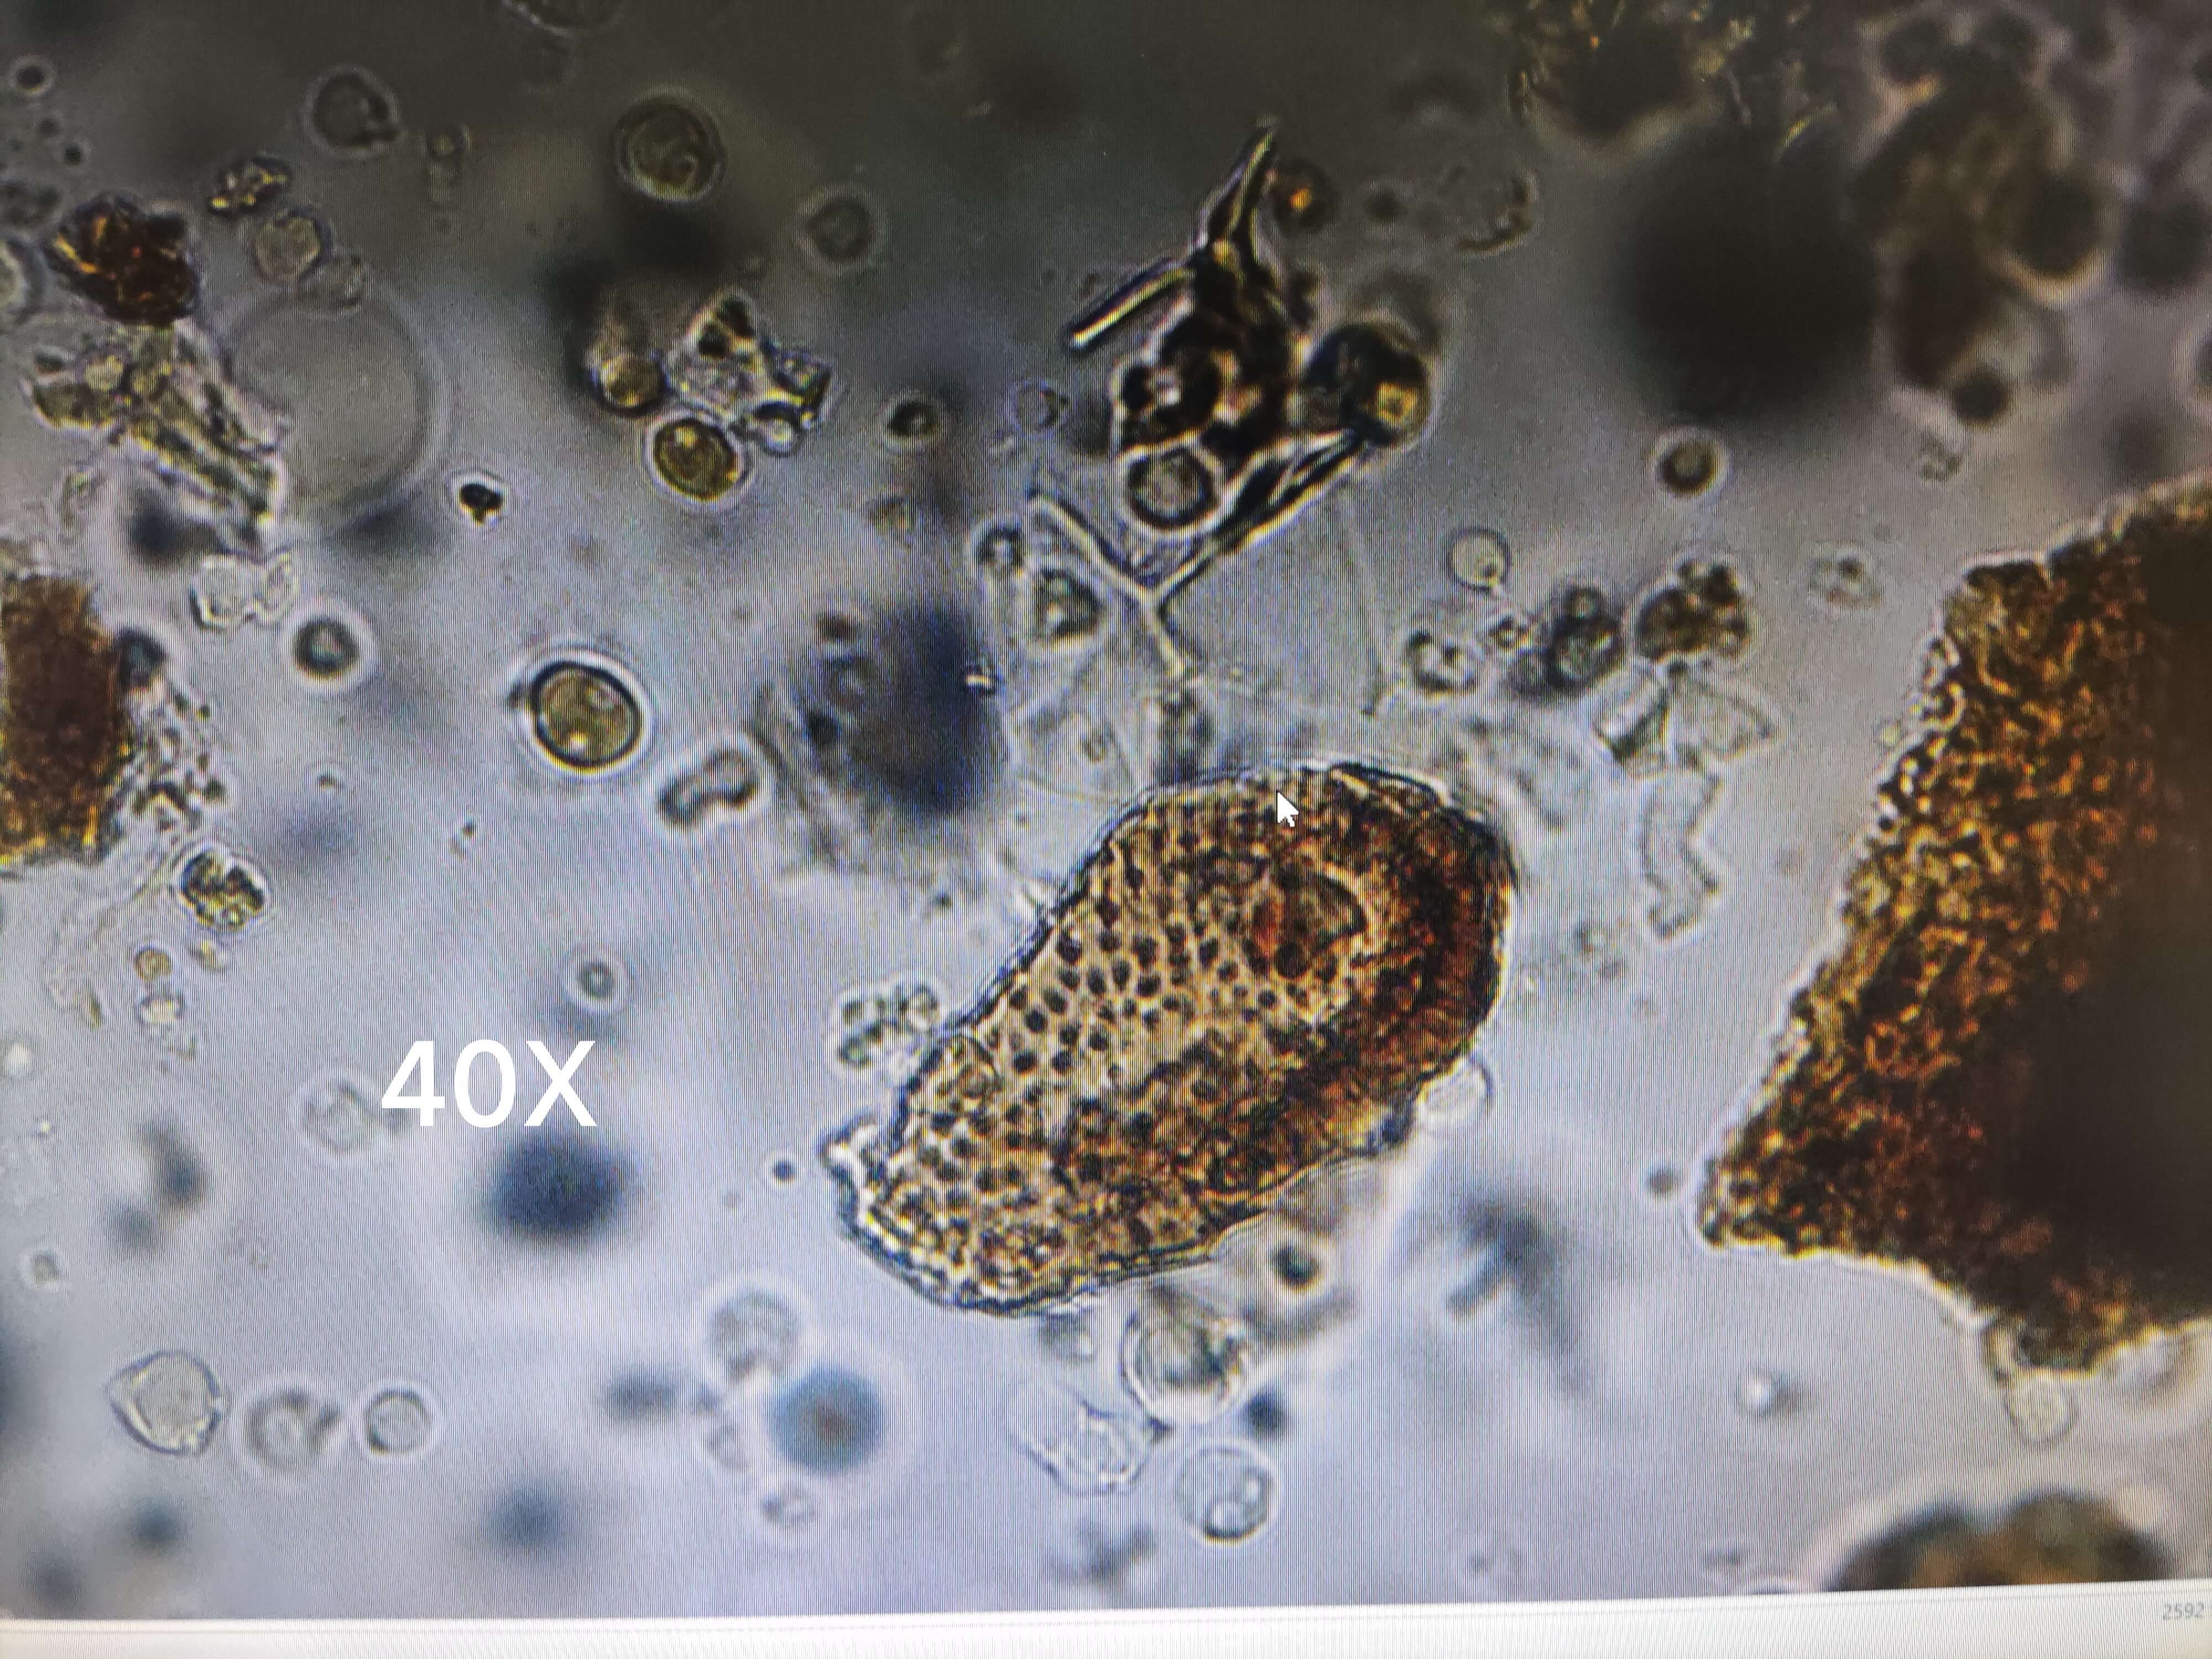

黄连

| 黄连 |

|---|

| 【参考文献】 《中药鉴定学》(康廷国主编) |

| 【显微鉴别】 粉末黄棕色或黄色。石细胞为类方形、类圆形、类长方形或近多角形,直径25~64μm,长至102μm,黄色,壁厚,壁孔明显。中柱鞘纤维黄色,纺锤形或梭形,长136~185μm,直径27~37μm,壁厚。木纤维较细长,壁较薄,有稀疏点状纹孔。木薄壁细胞类长方形或不规则形,壁稍厚,有纹孔。鳞叶表皮细胞,绿黄色或黄棕色,细胞长方形或长多角形,壁微波状弯曲,或作连珠状增厚。⑥导管为网纹或孔纹,短节状。 |

| 【显微重点】 石细胞、中柱鞘纤。 |

| 【图谱来源】 《中药成方制剂显微图典》 |